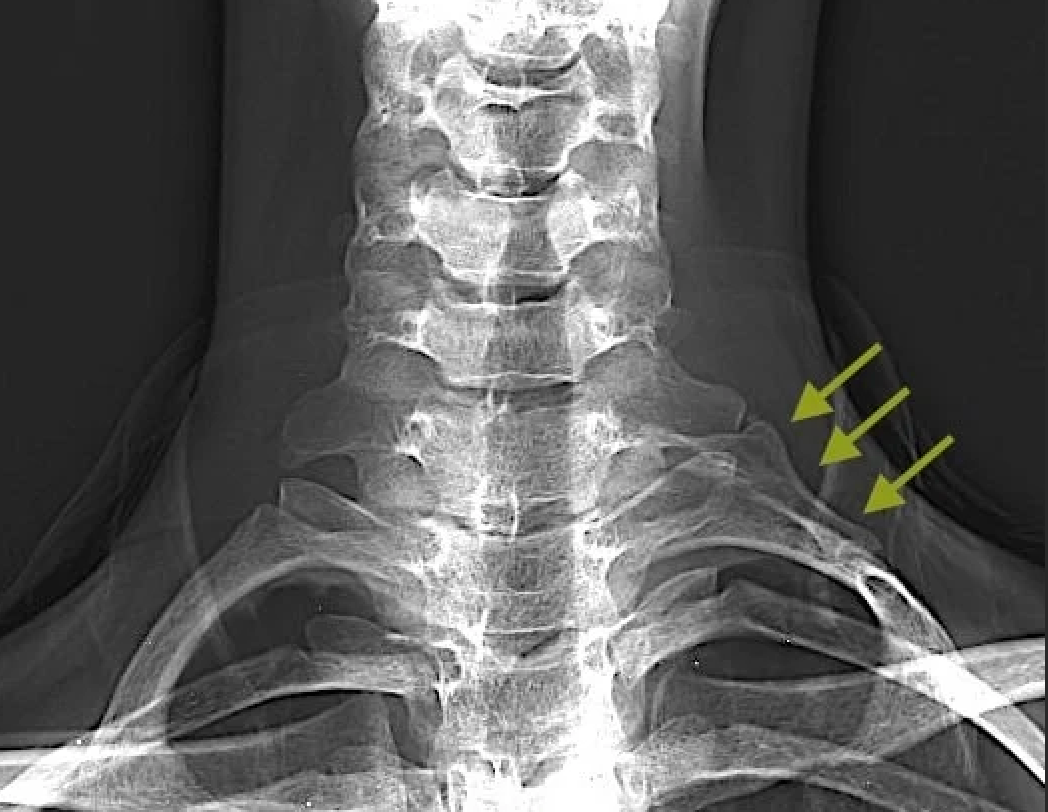

- Дополнительное шейное ребро

В норме у человека насчитывается 12 пар ребер, которые формируют грудную полость. У некоторых людей могут встречаться дополнительные шейные ребра. Согласно крупному литературному обзору, такие ребра обнаруживаются примерно у 1,1 % населения. Интересно, что среди пациентов с синдромом грудного выхода частота наличия добавочных шейных ребер достигает 29 %, что примерно в 25 раз превышает показатели общей популяции.